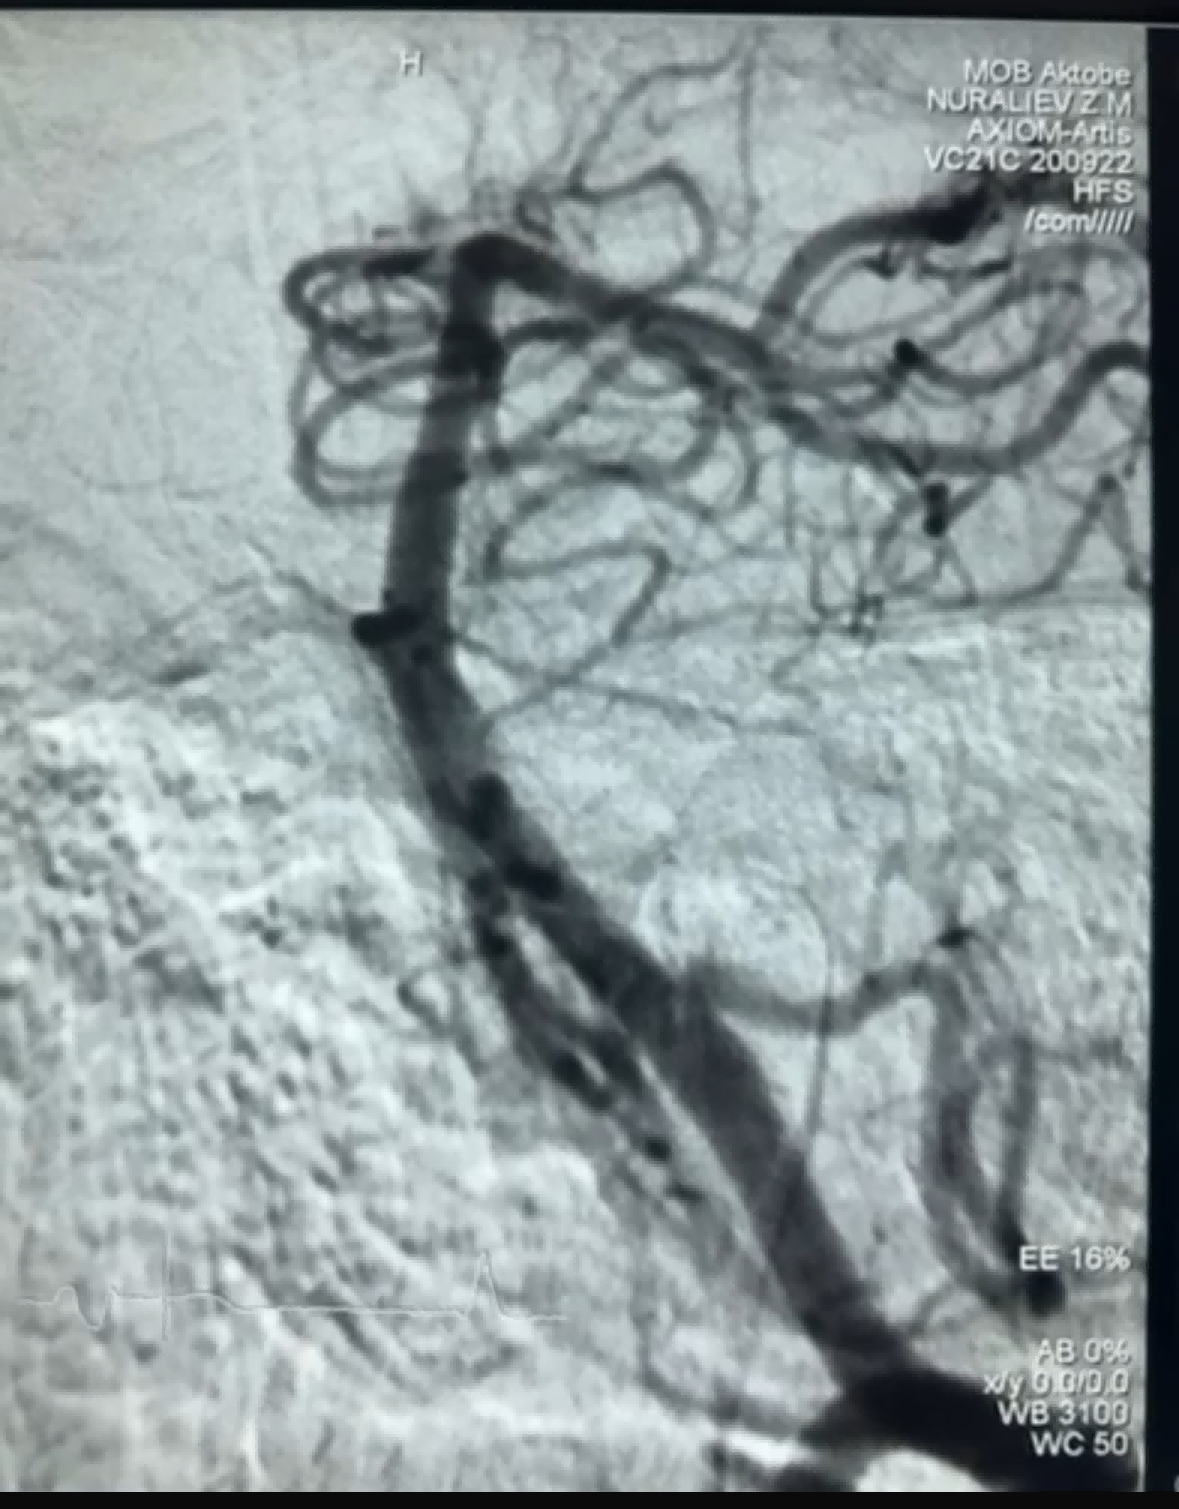

اخیراً یک مورد ترومبکتومی موفقیت آمیز با استفاده از Dredger Stent Retriever شرکت NeuroSafe Medical Co., Ltd. وجود دارد. Stent Retriever دارای یک نوک نرم غیر تهاجمی است که تا حد زیادی خطر آسیب انتیما را کاهش می دهد و دارای یک سوراخ منحصر به فرد به شکل خاص است. طراحی که لخته های خون را عمدتاً با بستن تغییرات شکاف جمع آوری می کند.